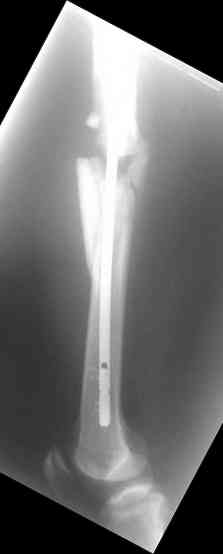

Re: С3-перелом бедра как лечить дальше?....

одна проблема в моей компьютерной неграмотности(не смог прикрепить снимки), а другая в том, что связь с пациентом потеряна и,насколько я понял в своем регионе ему посоветоваться не с кем, кроме главного врача который отреагировал на выбранную нами тактику так: "там тебя использовали в качестве подопытного кролика...".

Надеюсь сейчас показать перелом, а потом синтез.